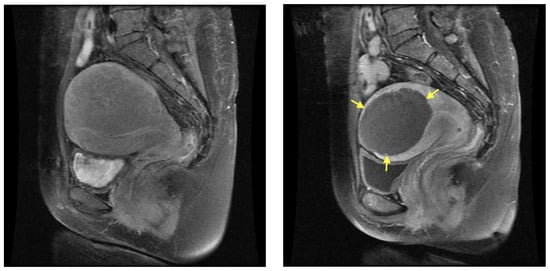

The median baseline volumes of the uteri and the measurable adenomyotic lesions were 446.6 cm3 (range: 240–1488.6 cm3) and 97.7 cm3 (range: 43.7–367.4) cm3, respectively. Table 3 summarizes the same volumes at 6 and 12 months after treatment, as well as the percentage volume reduction. Five patients (33.3%) had adenomyosis in the anterior uterine wall, nine (60.0%) in the posterior wall, and one (6.7%) in both the anterior and posterior walls. The images of one of the patients before and 6 months after HIFU are shown in Figure 3.

Figure 3.

Magnetic resonance (MR) images of adenomyosis from a 47-year-old woman: (Left) pre-HIFU MR image showing extensive adenomyosis involving mostly the posterior fundal uterine wall; (Right) post-HIFU MR image, 6 months after treatment, showing a hypoperfused well-defined area (arrows) as the result of HIFU.